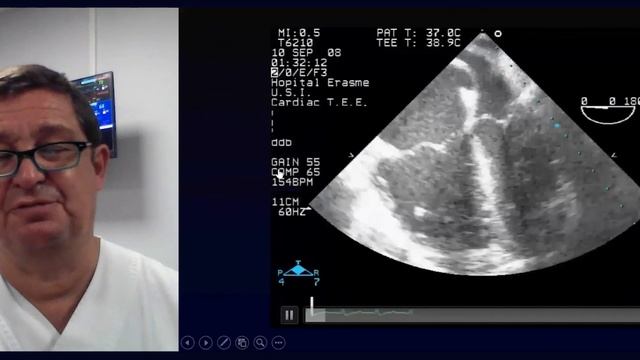

12+19:18Perioperative hypotension and vasopressors - Effect on visceral perfusion Daniel De Backer 20199просмотровгод назад